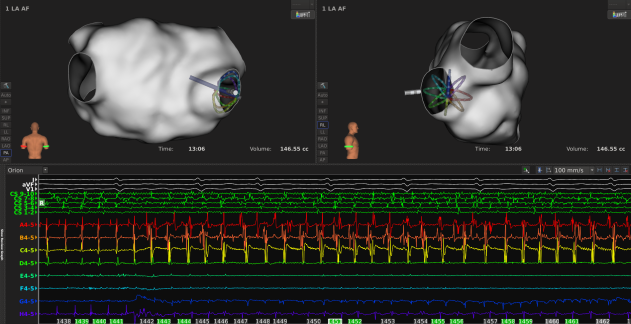

手术过程:

ABL strategy:CPVI+顶部线+后壁底部线+MVI

一:判断导管贴靠方面

1

通常导管良好贴靠时,健康心肌的LI值会相较血池阻抗升高10-20Ω,且数值保持相对稳定;

2

不同部位的LI值略有不同,但当LI值>140Ω,要注意区分是进入肺静脉内等特殊结构还是贴靠过紧?

3

导管移动或贴靠不稳定时,LI曲线波动剧烈,实时LI数值变化较大;

二:评估消融损伤方面

消融过程中LI稳定下降,通常5-8s到达平台期;

到达平台期后,最大LI下降值通常在15-25Ω范围内,提示消融有效;

消融过程中也要结合电位判断消融效果,通常阻抗下降至平台期后,MiFi微电极电位下降或消失明显,继续放电5s;